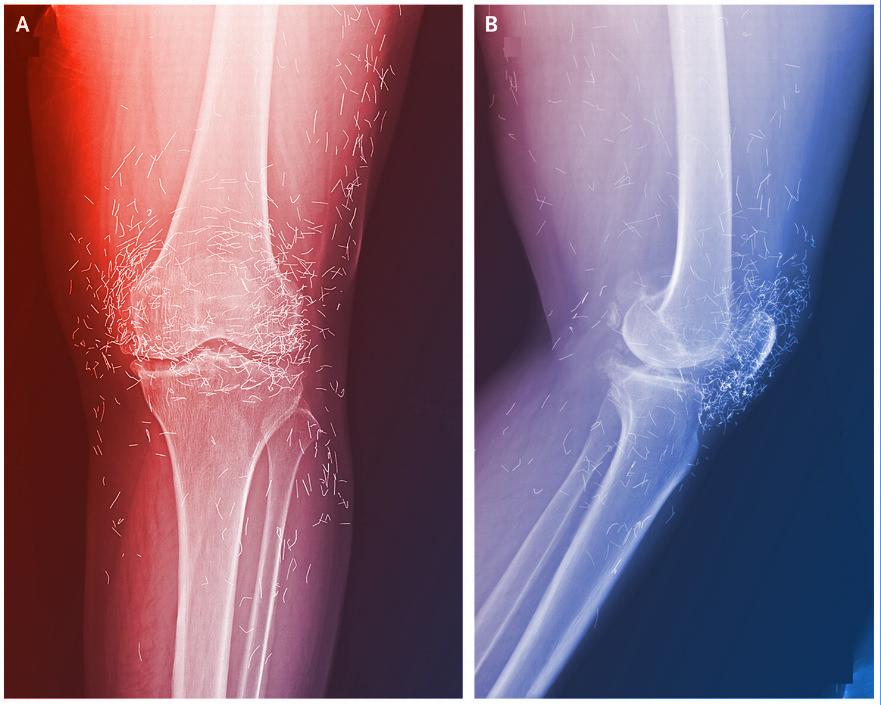

Kétségbeesésében a nő alternatív gyógymódokhoz fordult: kezdetben heti, majd egyre sűrűbb akupunktúrás kezeléseken vett részt. Amikor fájdalmai súlyosbodtak, kórházba ment, ahol röntgenvizsgálatot végeztek. Az orvosok megdöbbenésére a bal térdízületben a sípcsont belső részének megvastagodását, csontkinövéseket, valamint rengeteg apró foltot láttak a felvételen.

A furcsa foltokról kiderült: ezek steril, rövid aranyszálak, amelyeket egyes ázsiai akupunktúrás technikákkal ültetnek a bőr alá, hogy tartós ingerlést biztosítsanak. Dél-Koreában ez elterjedt módszer a térd- és reumás ízületi gyulladás kezelésére, annak ellenére, hogy semmilyen bizonyíték nincs a hatékonyságára.